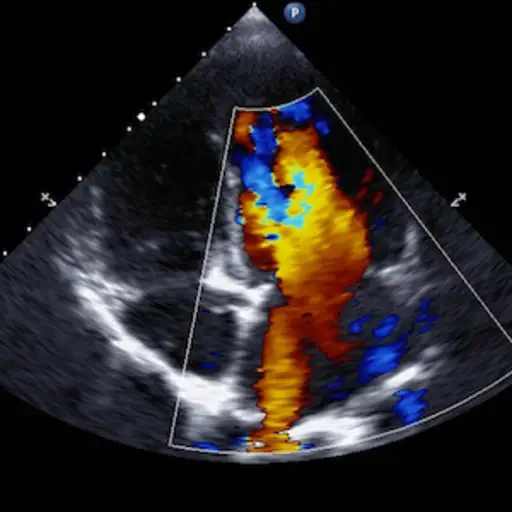

超声心动图:第1部分

一个超声心动图是一种非侵袭性,无痛的测试,允许心脏病学家看看你的心是否正常运作,或者如果它被扩大或削弱或有损坏的阀门。超声波通过胸部指向心脏。声波的回波被处理并用于生产心脏的图像。

超声心动图:第2部分

另外,可以通过使超声探针(在用喉部用药之后和适当的镇静后吞噬药物和适当的镇静)来进行化学激发超声心动图(TEE)。TEE提供从食道的心脏的特写图像。这种技术是寻找阿里亚血栓的绝佳方式。您的医生可以要求您在电气心致或导管消融之前具有TEE。